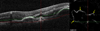

Purpose: To describe image artifacts of optical coherence tomography (OCT) angiography and their underlying causative mechanisms. To establish a common vocabulary for the artifacts observed.

Methods: The methods by which OCT angiography images are acquired, generated, and displayed are reviewed as are the mechanisms by which each or all of these methods can produce extraneous image information. A common set of terminology is proposed and used.

Results: Optical coherence tomography angiography uses motion contrast to image blood flow and thereby images the vasculature without the need for a contrast agent. Artifacts are very common and can arise from the OCT image acquisition, intrinsic characteristics of the eye, eye motion, image processing, and display strategies. Optical coherence tomography image acquisition for angiography takes more time than simple structural scans and necessitates trade-offs in flow resolution, scan quality, and speed. An important set of artifacts are projection artifacts in which images of blood vessels seem at erroneous locations. Image processing used for OCT angiography can alter vascular appearance through segmentation defects, and because of image display strategies can give false impressions of the density and location of vessels. Eye motion leads to discontinuities in displayed data. Optical coherence tomography angiography artifacts can be detected by interactive evaluation of the images.